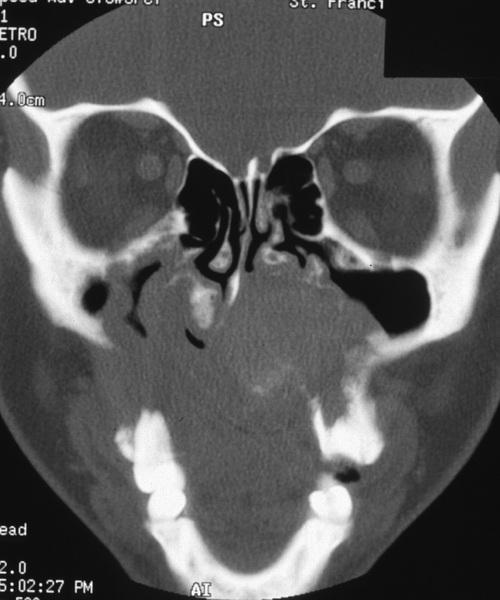

Computed tomography (CT) scan of this massive palatal tumor shows extensive destruction of the hard palate with extension of the tumor into the nasal cavity and both maxillary sinuses.

adenoid cystic carcinoma